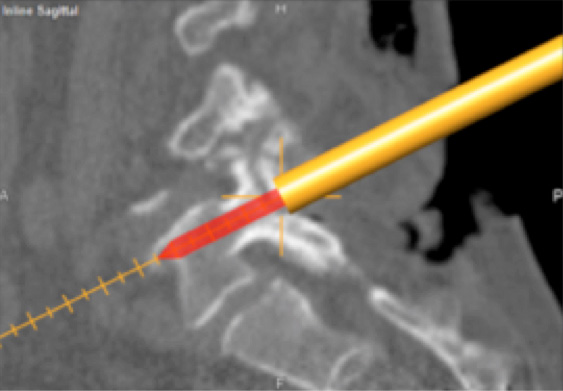

Conducted the first-ever dose escalation study using convection-enhanced delivery for diffuse intrinsic pontine glioma to bypass the blood-brain barrier and administer a drug directly to a brain stem tumor site